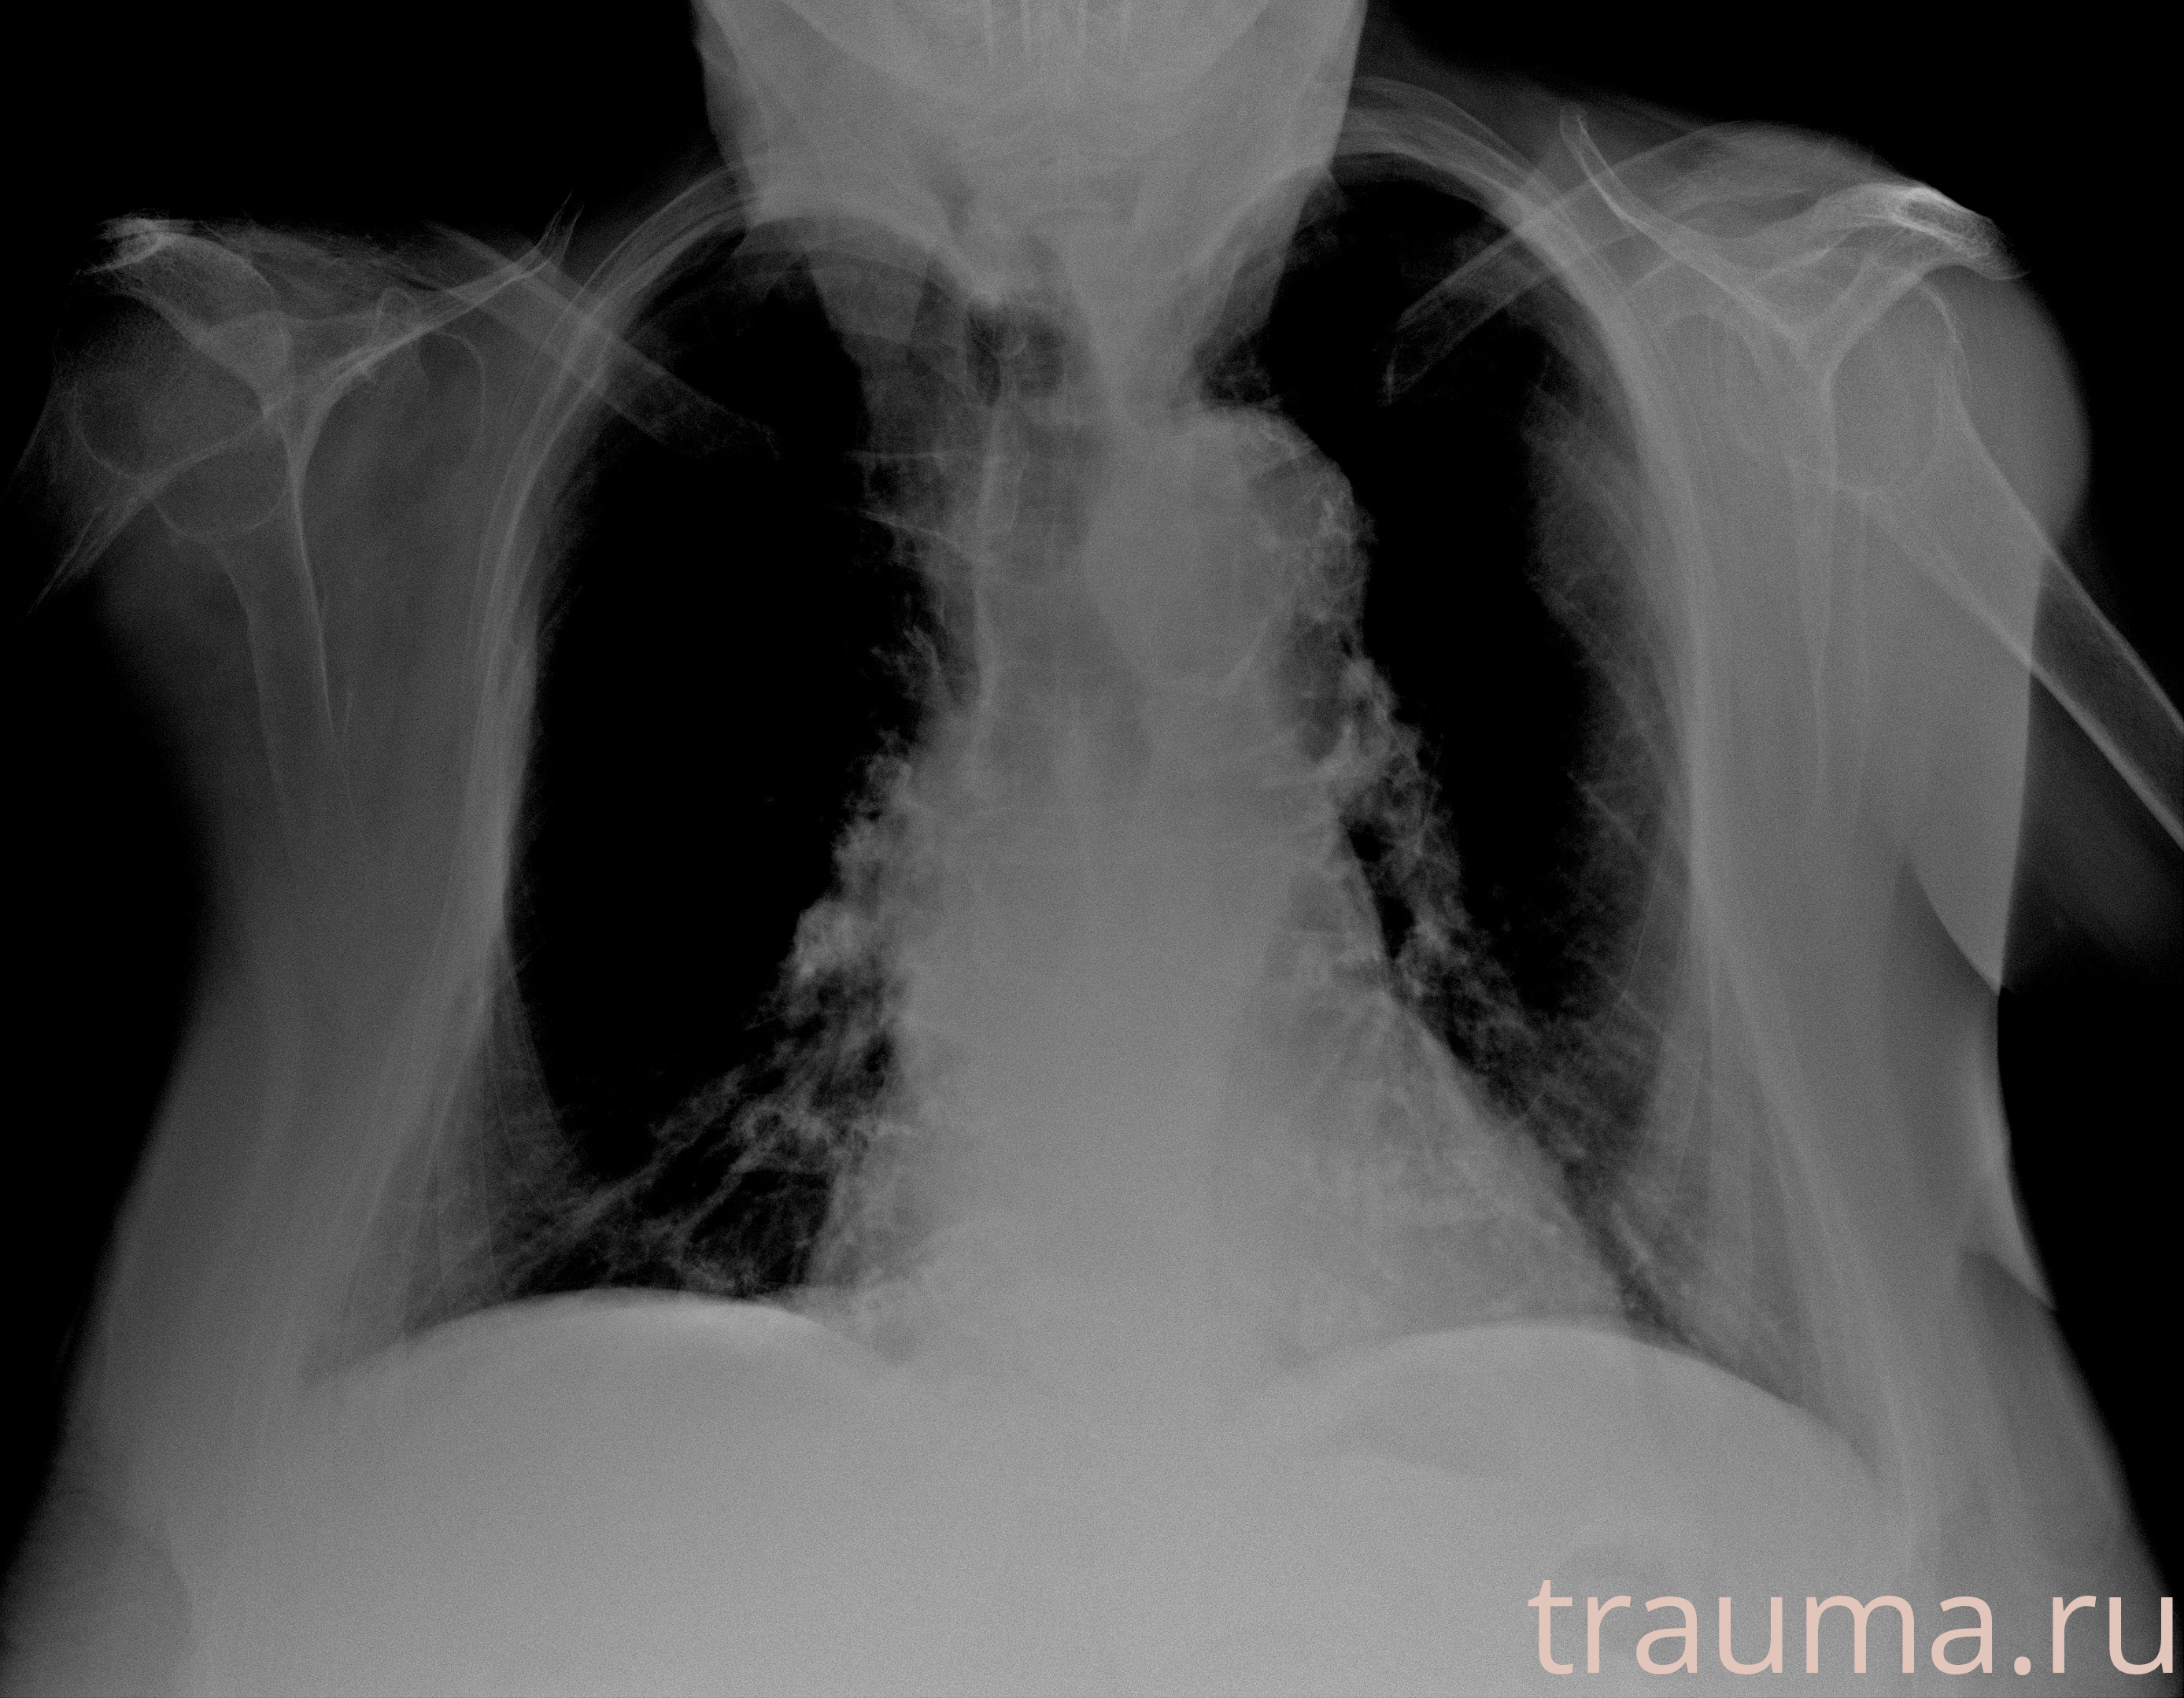

Рентген на дому: по вашему адресу приезжает врач-рентгенолог, травматолог-ортопед с мобильным рентгеновским аппаратом, проводит диагностику травмы или заболевания, делает необходимые рентгенограммы, дает рекомендации по дальнейшему лечению. Получить качественные снимки в домашних условиях возможно благодаря уникальной методике, разработанной МосРентген Центром для института  Склифосовского

при переломе шейки бедра и пневмонии от компании МосРентген Центр - партнера Института имени Склифосовского